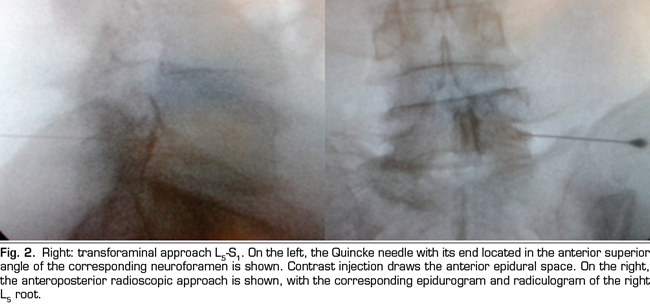

The procedure was performed in the surgical room. A peripheral venous catheter was placed with the patient on ventral decubitus position. Asepsis was conducted with alcoholic chlorhexidine and the local anesthesia was performed with 0.5 % lidocaine. Eighteen 3 1/2 or 4 3/4 inches tuohy needles (depending on patient size) were used for the parasagittal interlaminar technique. In the anteroposterior radioscopic view, the needle was inserted into the L4-5 or L5-S1 interlaminar spaces, using the tunnel vision technique, homolateral parasagittal of the side corresponding to the radicular pain (Figure 1). Loss of resistance was performed with saline. In the lateral view, a 4 mL contrast injection (Omnipaque©) was administered and the presence of anterior, posterior or both epidurograms was recorded (Figure 1). In the anteroposterior view the presence of radiculogram was recorded (Figure 1). A vial of betamethasone (12 mg of a mixture of phosphate and betamethasone acetate in 2 mL of solution) was then administered diluted with 3 mL of 0.5% lidocaine (total solution: 5 mL). The technical quality of the procedure was determined with the presence of paresthesia or concordant pain during the injection, and radiological data such as presence of radiculogram (Figure 1). Twenty two, 3 1/2 or 4 3/4 inches quincke needles were used in the transforaminal group and inserted using the oblique, lateral and anteroposterior radiological views.

The technical quality of the epidural steroid injection was evaluated in 21 out of 26 procedures performed with the parasagittal interlaminar approach. Anterior epidurograms, that is, achievement of the solution on the ventral epidural space, was obtained in 15 (71 %) of the patients (Figure 1 left); 17 (85 %) patients referred pain or paresthesia in the radicular territory during the injection, and a radiculogram was found in 12 (60 %) patients.